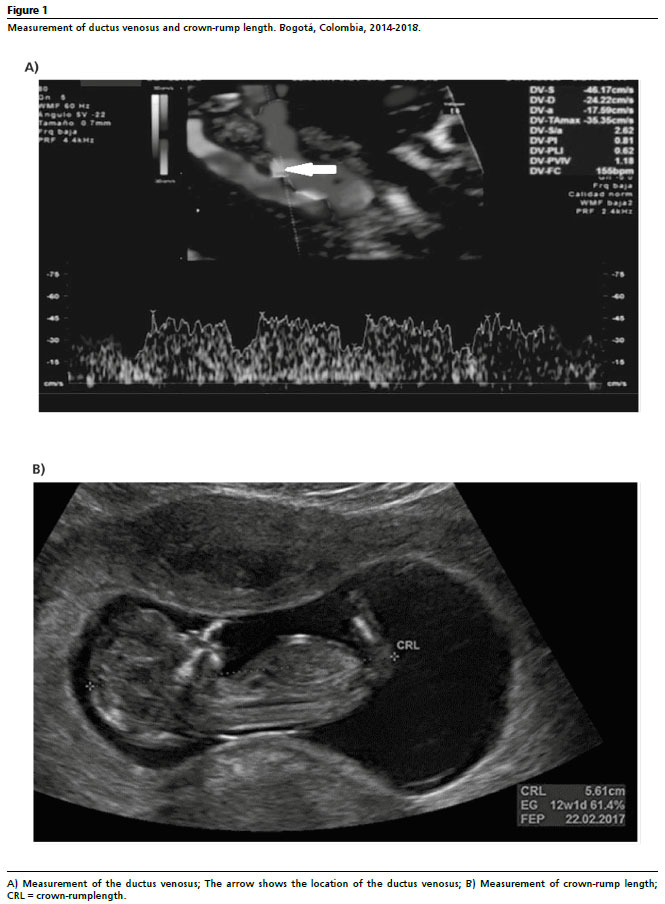

Patients attended ultrasound evaluation during the first trimester between week 11 and week 13 and 6 days, where the sociodemographic, clinical, ultrasound (nuchal translucency [NT] and CRL), and gynecologic-obstetric variables (parity, history of full-term and preterm delivery, preeclampsia, and intrauterine growth restriction [IUGR]) were recorded.Fetal DV characteristics (pulsatility index and flow waveform) were assessed during fetal quiescence via ultrasound in a midsagittal plane with the fetuslying on its back. The image was enlarged until the fetal thorax and abdomen could be seenclearly. Subsequently, the DV that connects the umbilical vein with the inferior vena cava was visualized usinga color Doppler and medium insonation through the fetal abdomen at the hepatic level, where greater turbulence was observed, with an insonation angle of less than 30 degrees. Finally, the DV waveform was acquired using pulsed Doppler with a sample volume between 0.5 and 1.0 mm (Figure 1A),

18,19 and the DV normality references reported by Borrell

et al.

20 were used for the study. The CRL was measured on a sagittal plane by enlarging the image and with the fetus in a neutral position and measuring the maximum length of the fetus from the outer side of the crown of the head and to the rump. Gestational age was calculated and confirmed based on this measurement (in cm) taken using ultrasound from 11 to 13.6 weeks of gestation (Figure 1B).